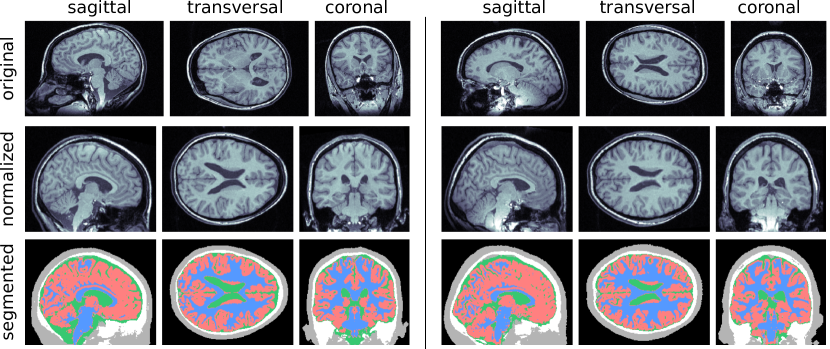

Figure 5(a) shows two representative individuals in the segmentation steps to compute the static component of the atlas. The first row contains the original images, the second row contains the normalized images and the third row show the segmented tissues. Figure 5(b) shows the average over the characteristic functions of all individuals and for each segmented tissue. A voxel with a value equal to 1.0 indicates it was classified as the same tissue in all images.

Figure 5: Static atlas computations. (a) Processing steps of two representative individuals of the dataset. The first row shows the original images, the second presents the results of the normalization and the third row the result of the segmentation. GM: red, WM: blue, CSF: green, BO: white, and OT: grey. (b) Average of the characteristic functions 𝝌tsubscript𝝌𝑡\bm{\chi}_{t} for each tissue.